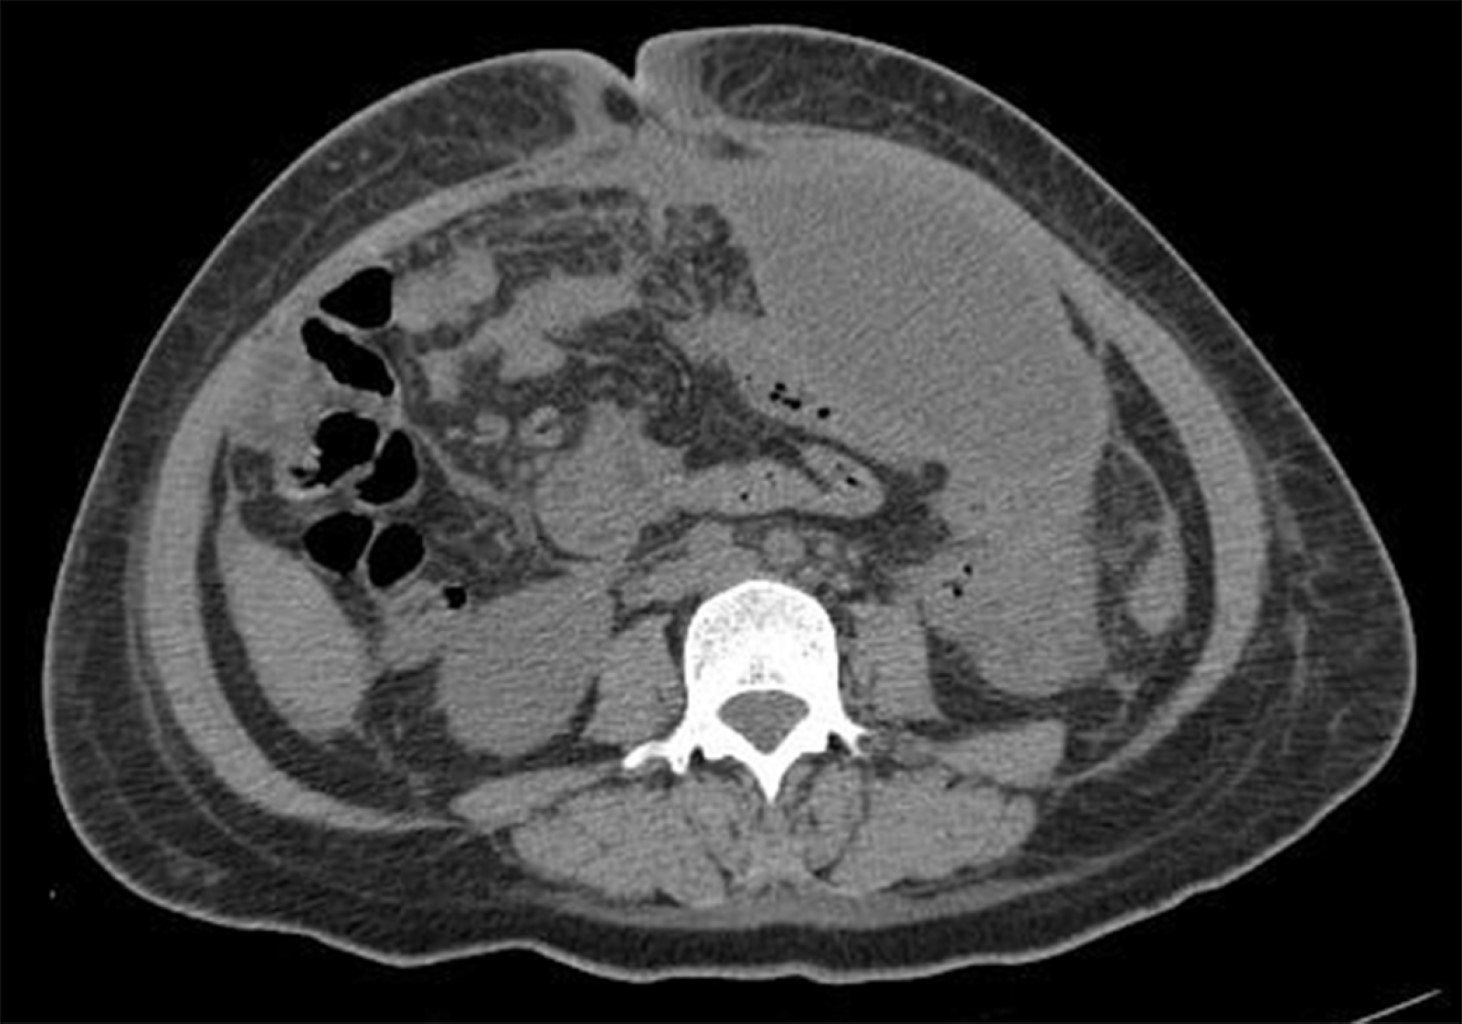

Paciente femenino de 40 años de edad, gesta cuatro, partos tres, con antecedente de estenosis valvular aórtica desde 2017 con manejo quirúrgico a base de colocación de prótesis valvular y acenocumarina hasta el diagnóstico de su último embarazo, durante el cual se suspende anticoagulante oral e inicia enoxaparina. Inicia padecimiento actual al ingresar al servicio de obstetricia con reporte de edad gestacional de 28.5 semanas de gestación (SDG) por última menstruación y de 29.4 por fetometría. Se diagnostica preeclampsia con datos de severidad, por lo que se decide realizar cesárea tipo Kerr y oclusión tubaria bilateral con técnica de Kroener, reportando 350 cm3 de sangrado, obteniendo producto único vivo, masculino, 31.5 semanas por Capurro, Apgar 7/8, con labio y paladar hendido. Egresa al quinto día requiriendo transfusión de hemoderivados en su postquirúrgico inmediato. Veintiún días después reingresa por sangrado abundante y fétido a través del abordaje quirúrgico, se hace curación y se evidencia defecto de pared abdominal, por lo cual se decide realizar ultrasonido, con hallazgos de defecto de pared anterior del abdomen en porción cefálica de la herida a través del cual protruyen asas intestinales (Figuras 1 y 2), en tomografía de abdomen se identifica colección heterogénea no medible en tercio medio y caudal de herida a nivel del plano subcutáneo, así como colección de pared gruesa en cavidad pélvica y fosa iliaca izquierda (Figura 3).

Figura 3